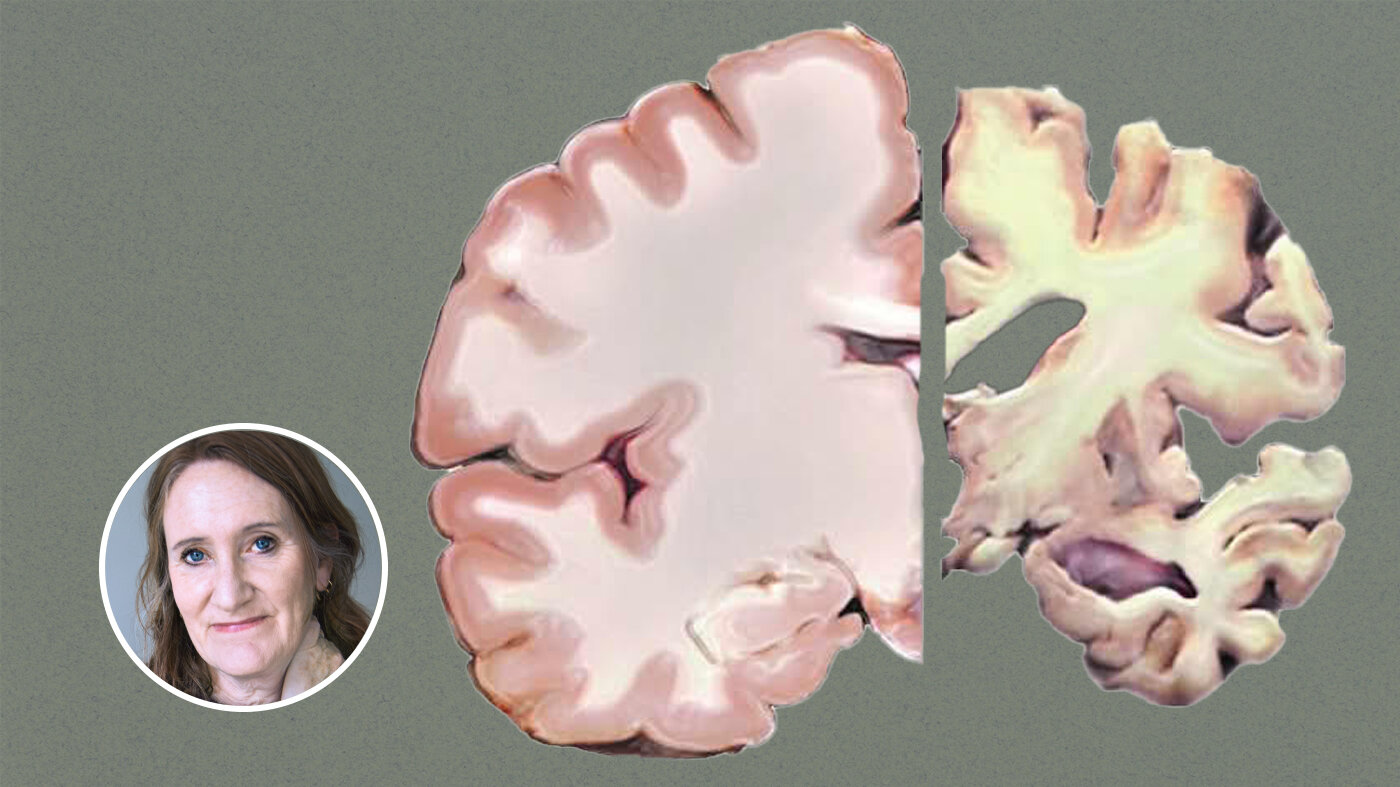

Demens har størst sannsynlighet for å ramme eldre over 65 år. Derfor viser Sykepleien en hjerne med «utløpsdato» på forsiden av denne utgaven. Ironisk ment, selvfølgelig.